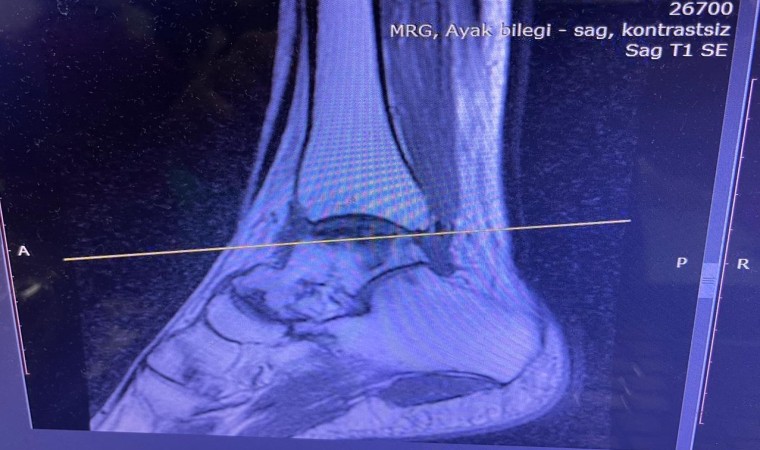

Sağlık alanındaki teknolojik gelişmelerin ve güncel uygulamaların yakından takip edildiği Balıkesir Üniversitesinde gerçekleştirilen ameliyatla ilgili bilgiler veren Ortopedi ve Travmatoloji Anabilim Dalı Öğretim Üyesi Doç. Dr. Aziz Atik; “Lenf kanseri olan 21 yaşındaki hastamız lenf kanseri tedavisi görerek sağlığına kavuşmuş ancak ilerleyen zamanlarda aldığı tedavilerin yan etkisi olarak ayak bileği kemiğinde çürüme meydana gelmiş. Bize başvuran hastamızın eklem yüzeyi bozulmuş ve hastamız yürümekte zorlanıyor, topallıyordu. Büyük bir lezyonu olan hastamıza büyük lezyonlarda uygulanan en iyi tedavi yöntemi olan ve nadir olarak yapılan bir ameliyatla kadavra donörden kemik ve kıkırdak doku nakli gerçekleştirdik.” ifadelini kullandı. Ülkemizde kemik ve kıkırdak bankası olmadığının altını çizen Doç. Dr. Aziz Atik, yurt dışından bir donör bulmak için çalışmalar yaptıklarını ve yurtdışından kemik bulunduğunda ivedi bir şekilde ameliyatı gerçekleştirdiklerini söyledi. Ameliyatın son derece başarılı geçtiğini belirten Doç. Dr. Aziz Atik, güzel bir eklem düzeyi elde ettiklerini ve ameliyatla genç bir insanın topallamadan, ağrısız yürümesini hedeflendiklerini dile getirdi.